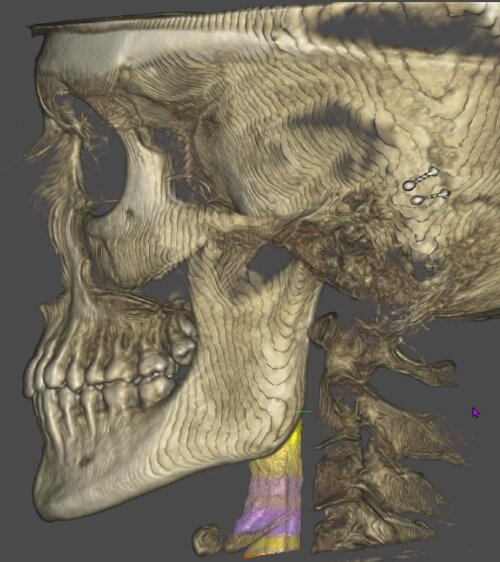

my major failos as you can see from the pics are midface/paranasal deficiency (look how much setback my nasal base is), negative orbital vector (but i suppose a qlf1/2, hlf1, USO would fix this without further procedures), nasolabial folds, malar fullness due to lack of skeletal tissue, flat face etc.

my major failos as you can see from the pics are midface/paranasal deficiency (look how much setback my nasal base is), negative orbital vector (but i suppose a qlf1/2, hlf1, USO would fix this without further procedures), nasolabial folds, malar fullness due to lack of skeletal tissue, flat face etc.